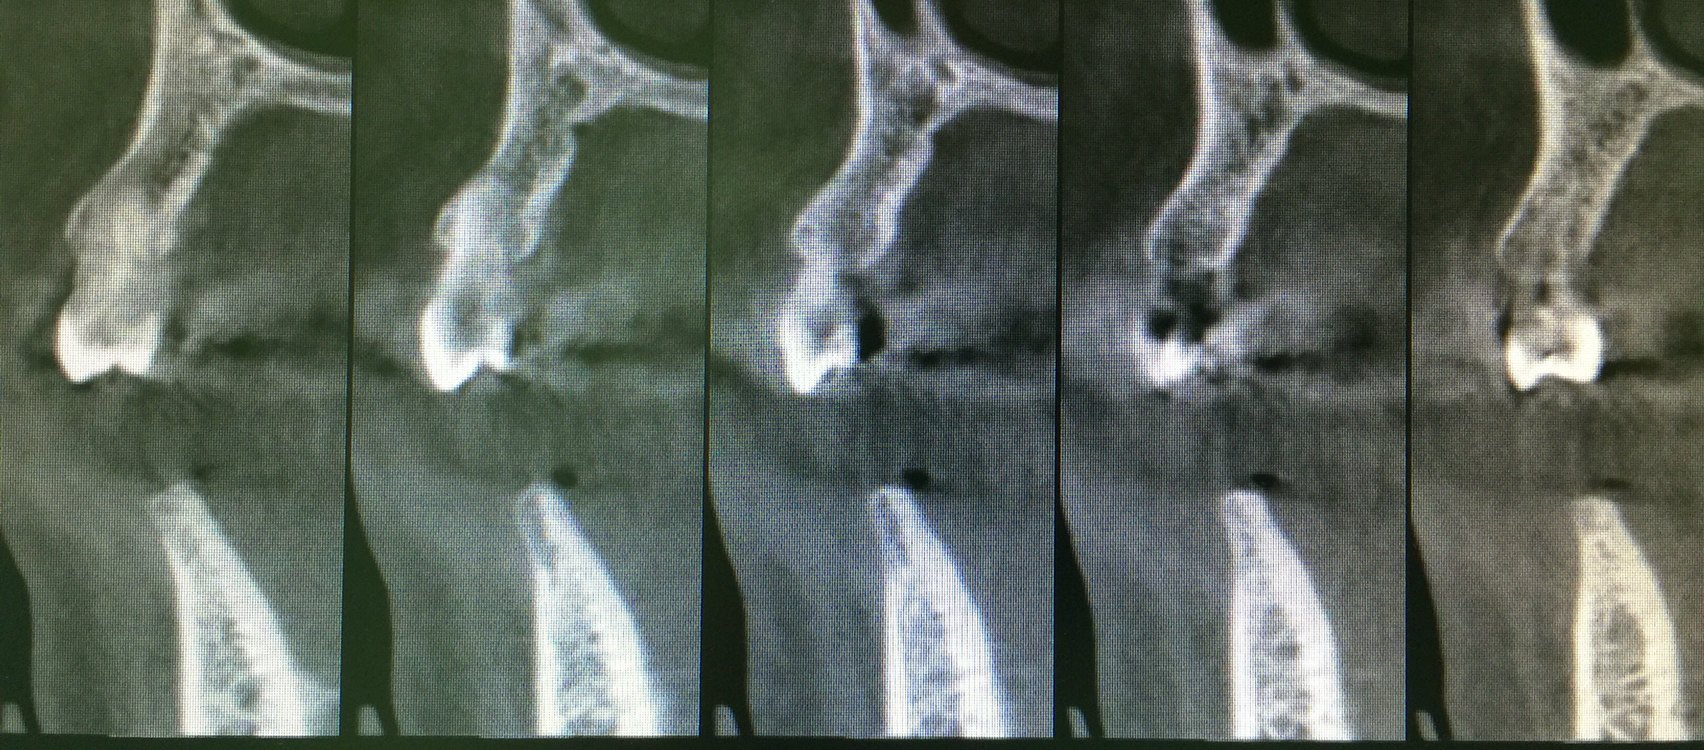

這就需要CT檢查,下圖是口腔CBCT的結果,我們看到缺牙區(qū)的牙槽骨寬度極窄處只有不到3毫米,顯然不是理想的種植牙條件。如果臨床檢查寬度理想,全景片檢查高度理想的情況下,就可以不用拍口腔CBCT。

口腔CBCT